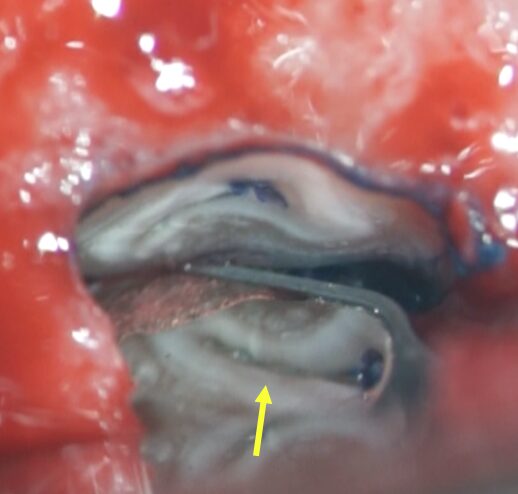

• 青色の細菌の染め出し液で感染源のイスムスが発覚(青矢印)。根管治療で殺菌が届かない場所です。

• イスムスを削除しながら逆根管形成を行い、お薬(バイオセラミックパテ)を充填したところ(黄色矢印)。

抜歯時に360度歯根を顕微鏡でチェックを行う。青い染め出し液を使い破折がないかを確認。今回は幸い破折はありませんでした。

根管の根管の間の繋ぎ目(赤矢印)。